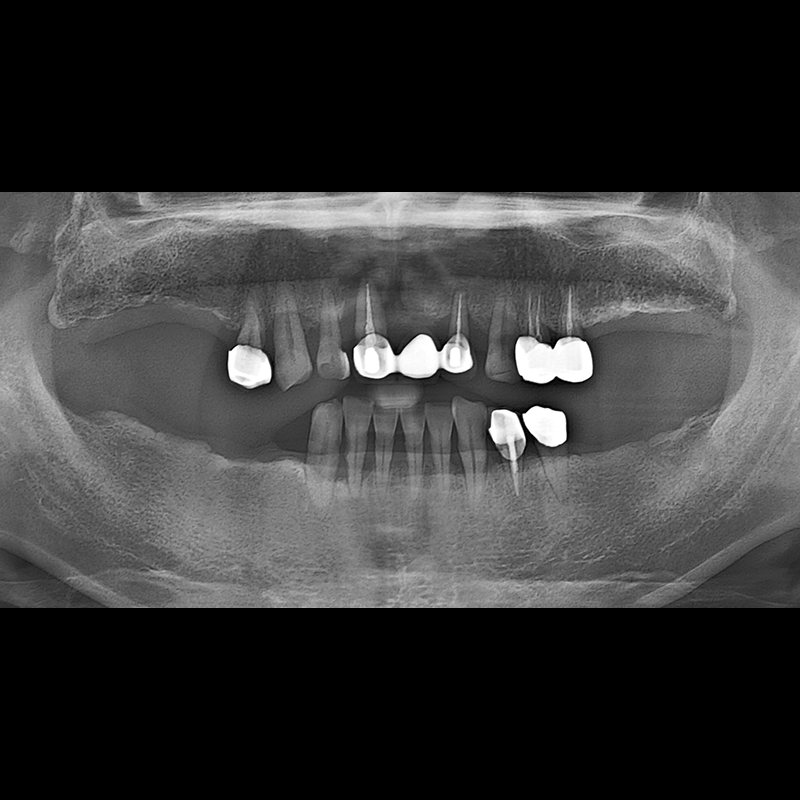

BEFORE AFTER

임플란트 전후사진 2025.05.30

결손된 치아 부분과 살리기 힘든 치아 위치에 임플란트를 식립하였습니다.